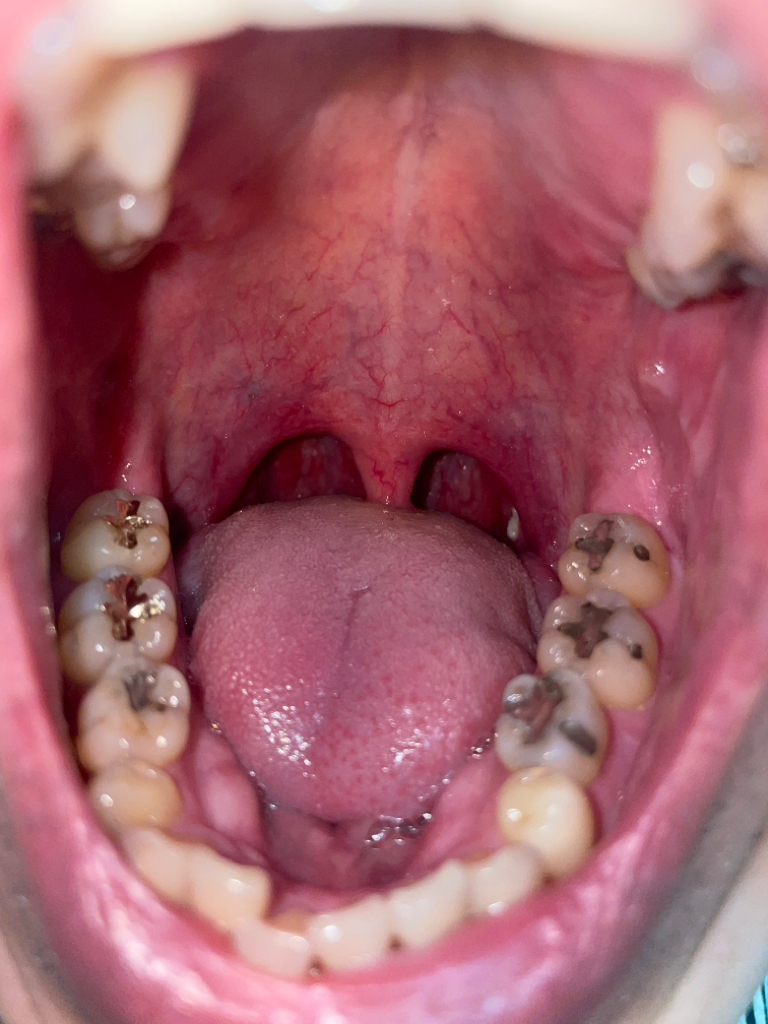

사진상에 보시면 목젖 뒤에 오른똑 자그맣게 하얀 부분 보이시나요?? 이런적은 처음인데 왜 저러런건가요??일주일은 안댓고 한3-4일 된거 같아요

• 2번 째 사진